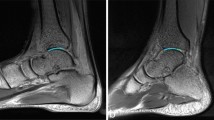

Ultrasonography was used to measure the cartilage thickness of the metacarpal heads of the second, third, fourth, and fifth digits. All measurements were performed using a high-frequency linear array transducer (SONON 500 L; Healcerion Co., Ltd., Seoul, South Korea) with a frequency range of 6–12 MHz. Participants were seated comfortably with the hand resting on a flat surface and the fingers gently flexed into a loose fist. The transducer was oriented longitudinally over each metacarpal head with no direct pressure applied to the cartilage surface. A generous amount of coupling gel was used to ensure full acoustic contact and to eliminate transducer compression artifacts. The transducer was maintained in a hover position slightly elevated above the skin to prevent deformation of the underlying tissue, while the probe angle was kept perpendicular to the cartilage surface to avoid anisotropic distortion. An experienced musculoskeletal ultrasound researcher in the field performed all imaging. The sonographer was blinded to the participants’ injury history during the measurement process to minimize bias. To enhance reliability, each site was scanned three times, and the mean value was used for analysis. The measurement sites were first localized by palpation of the metacarpophalangeal joints. Cartilage thickness was measured at the central point of the hypoechoic band corresponding to the hyaline cartilage layer, using ImageJ software (National Institutes of Health, Bethesda, MD, USA) (Fig. 3).